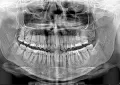

Мне 35+. 4 дня назад врач стоматолог лечил кариес. На зубе установил пломбу с краю и прикрепил ее к старой пломбе в центре зуба. Когда врач начала лечить сказала, что кариес не глубокий. Дала в зеркало посмотреть рассверленную дырочку, была видна пульпа. Глубина дырочки 3 мм точно была и ширина порядочная. Итог. Зуб запломбирован светоотражающей пастой и побаливает. Пока не сильно. Ночью не беспокоит. Мягкое печенье не могу на нем есть, возникает резкая боль как сверлом, макароны могу. Пока не грызу ничего, не нагружаю. Это 7-й зуб, снизу, справа. Сегодня 4 день после лечения. Как проснулась, зуб болит не переставая. Нерв в зубе не умерщвлен.

Обратиться к врачу стоматологу-терапевту, который лечил Вам зуб. Может быть сделан рентгенографический снимок для полной диагностики.

Такие боли могут быть и из-за завышенной пломбы.